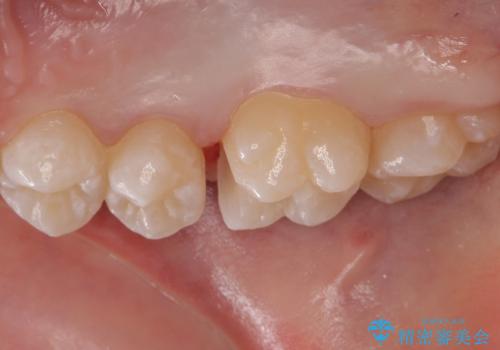

歯と歯の間の虫歯 セラミックインレーでの治療

- 検査の結果、レントゲン画像上で虫歯が確認されたため治療をしていくこととなりました。

白くて精度の高いものをご希望されたためセラミックインレーでの治療を行いました。

小さな段差もないような適合の良い修復物は他の修復物に比べて今後の虫歯リスクを抑えることができます。